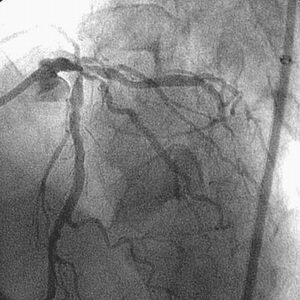

高度石灰化#1~#2と同#6/#9に対するRotablator依頼で他院から紹介され、PCIを

施行した86歳の男性です。3日前にRCAへRota-SESして、今回#6/#9へのPCIでした。

Baselineが『ChoicePT2BsLn』の3枚です。

7F lTFA(Arrow金属シース55cm)で7F Mach1 CLS4.0を使用、#9→#6の順に1.5mm burr

でRotablatorを行ない、2.0mmへサイズアップしました。2.5mmバルーンで#9→#6と拡

張し、#6に3.5mm×23mmのCypherを留置しました。3.5mmバルーンで#6を高圧(最

大22ATM)後拡張し、#9の2.5mmバルーンとともにSimultaneous kissing inflationを

施行、#6、#9ともに良好な開大を得ました。

しかし、KBT直前の像(『ChoicePT2.GW.Prolapse』)では屈曲していただけの#9に挿

入したChoice PT2 LSが、KBT時像からは屈曲とともに先端1cm程度が断裂し

(『ChoicePT2.GW.Fracture』)、#9の末梢枝に遺残してしまいました

(『ChoicePT2.Fnl』2枚)。幸い虚血所見がまったくありませんでしたので手技は終

了とし、術後のCK逸脱もなし、翌日お元気に退院されました。